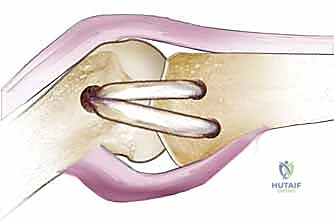

- الأربطة الجانبية الحقيقية (Proper Collateral Ligaments): وتشمل الرباط الجانبي الزندي (UCL) والرباط الجانبي الكعبري (RCL). تنشأ هذه الأربطة من حفر منخفضة على جانبي رأس عظم المشط، وتتجه بشكل مائل من الجزء الظهري القريب (Dorsal-Proximal) إلى الجزء الراحي البعيد (Volar-Distal). تندغم هذه الأربطة بقوة في الثلث الراحي من قاعدة السلامية الدانية.

- ملاحظة بيوميكانيكية هامة: هذه الأربطة تكون في أقصى درجات الشد والتوتر عندما يكون مفصل الإبهام في حالة انثناء (Flexion)، وتكون مرتخية نسبياً في حالة البسط (Extension). هذا يعني أن المفصل يكون أكثر استقراراً أثناء الإمساك بقوة.

- الأربطة الجانبية المساعدة (Accessory Collateral Ligaments): تقع هذه الأربطة في الجزء الراحي (الأمامي) قليلاً بالنسبة للأربطة الحقيقية. تنشأ من نفس المنطقة تقريباً وتمتد بشكل مائل لتندغم في العظام السمسمانية (Sesamoid Bones) والصفيحة الراحية (Volar Plate). على عكس الأربطة الحقيقية، تكون الأربطة المساعدة في أقصى درجات الشد عند بسط المفصل (Extension).

| الآلية والطريقة | استخدام جبيرة مخصصة للإبهام (Thumb Spica Cast/Splint) لتثبيت المفصل ومنع الحركة لمدة 4 إلى 6 أسابيع، تليها فترة تأهيل. | تدخل جراحي دقيق لخياطة الرباط المقطوع أو إعادة بنائه باستخدام رقعة وترية (Tendon Graft)، وتثبيته بخطاطيف عظمية. |